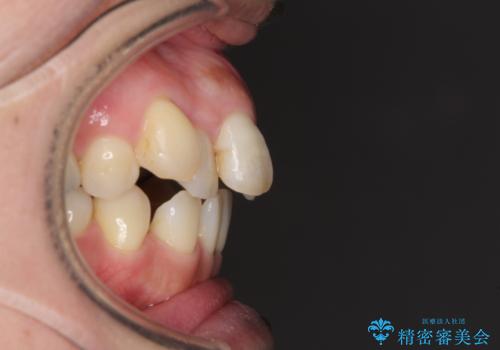

- 八重歯と前歯の隙間を気にして来院された患者様です。

下顎前歯は2本欠損しており、それが原因で隙間ができていました。

また、その影響で上下歯列がアンバランスとなっており、上下前が非接触となっていました。

上下のバランスを取って八重歯などを解消するため、上顎左右第1小臼歯を抜歯することとしました。

根管治療の必要な歯も2本あったため、まずは根管治療を行い、ワイヤー矯正の後に補綴治療を行うこととしました。